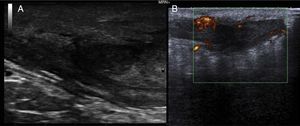

We report the case of a 51-year-old man who was referred to the dermatology department with a painful, suppurative nodule in his left groin that had appeared 1 year previously and was refractory to various antibiotic regimens prescribed by his primary care physician. The patient had a personal history of type 2 diabetes mellitus and was a smoker. Physical examination revealed an erythematous subcutaneous lesion with areas of suppuration in the lower left groin. On palpation, the lesion extended to the perineal region (Fig. 1). The examination also revealed 3 lesions that were clinically compatible with condylomata acuminata in the perianal area. He was diagnosed clinically for hidradenitis suppurativa (HS). Ultrasonography with an 18-MHz linear probe revealed the presence of a fistulous tract, with areas of fluid collection, together with intense vascularization on Doppler mode (Fig. 2). Given the location and depth of the lesion, the patient was sent to the clinic of the surgery department for complete removal of the lesion. Histopathology showed changes that were compatible with HS and well-differentiated squamous cell carcinoma (SCC) over the fistulous tract, which was located close to the deep resection margin. No vascular invasion or perineural infiltration was observed (Fig. 3 A and B). Extension of the surgical margins revealed no evidence of residual tumor, although foci suggestive of viral infection were observed (Fig. 3C). Immunohistochemical staining with p16 was intensely positive (Fig. 3D). Polymerase chain reaction and genotyping based on in situ hybridization with a microarray of paraffin-embedded tissue were performed to investigate the presence of human papillomavirus (HPV). The result was positive for genotype 6 (considered low risk); the same finding was recorded for the perianal condylomata acuminata. Laboratory analysis yielded negative results for HIV and hepatotropic viruses. After a 12-month clinical and imaging-based follow-up (computed tomography and magnetic resonance imaging of the pelvis), the patient showed no signs of local recurrence or metastasis.

Both ultrasound and magnetic resonance imaging could prove useful for confirmation of the true anatomical extension of the disease before surgery.10 Wide excision of the lesion is considered the standard treatment. SCC that arises in areas of chronic inflammation caused by HS is often well differentiated. Nevertheless, despite this theoretically good histologic prognosis, we can observe rapid growth, local aggressiveness, early metastasis, and high mortality.1